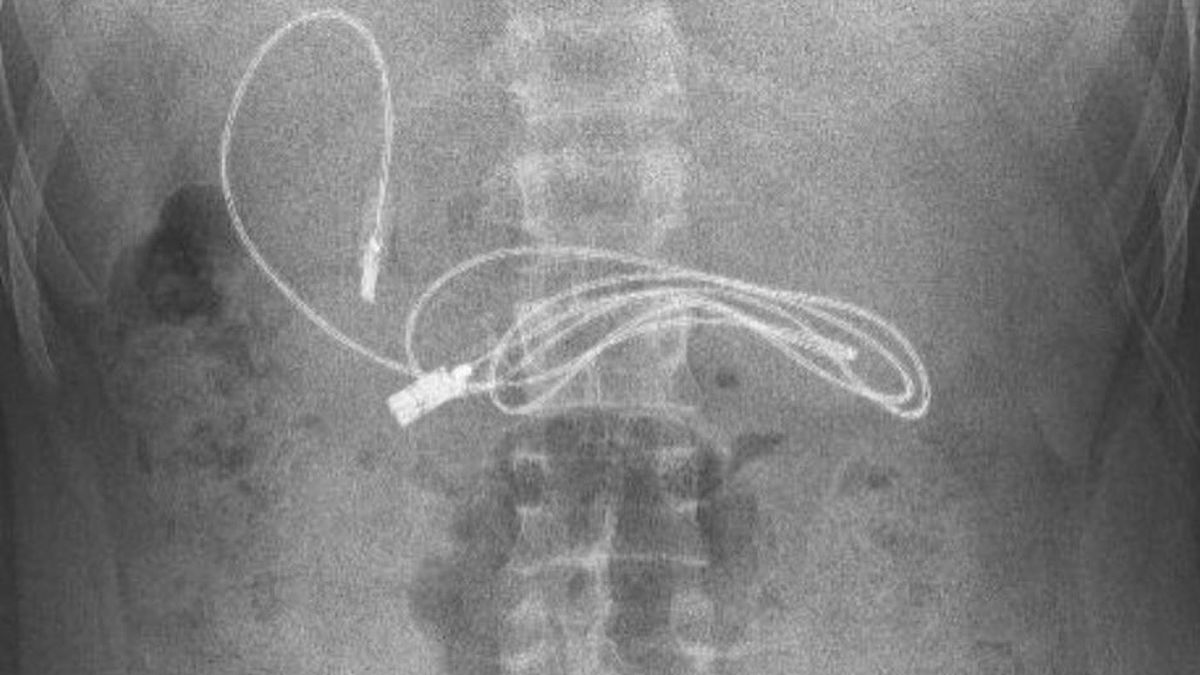

Djali 15-vjeçar u dërgua në spital nga familja e tij në Diarbakir, në juglindje të Turqisë. Megjithatë, kur mjekët i bënë një skanim me rreze X, ata mbetën të shqetësuar kur gjetën një pajisje të mbështjellë brenda stomakut të tij.

Ata u hutuan veçanërisht pasi në fillim ata e hoqën një lidhëse e flokëve, si dhe kablloja e gjatë. Dr Dogan tha për mediat lokale: "Padyshim që e kishim të vështirë të hiqnim kabllon, pasi njëra skaj i kabllit kishte kaluar në zorrën e hollë".

Kur kabllo u hoq, ekipi e doktorëve mbeti i hutuar nga gjatësia e saj, me kabllon e cila arrinte 90 centimetra gjatësi kur zgjatej. Doktor Dogan shtoi: “Pasi procedura përfundoi me sukses, pacienti u dërgua në shtëpi në gjendje të mirë shëndetësore”.